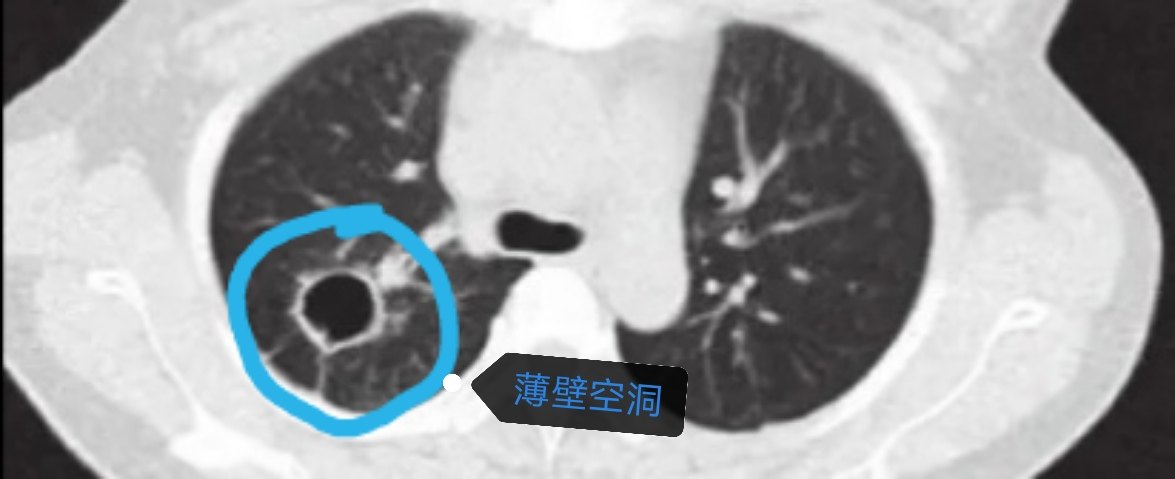

空洞型肺癌主要表现在CT上形成一个空洞,空洞壁厚薄不一,很薄的薄壁空洞看起来像肺大疱,厚壁空洞看起来像是肺炎实变后的眼睛?,空洞的形成机制仍不十分清楚,目前普遍认为厚壁空洞是由于肿瘤组织的缺血、感染及坏死导致肿瘤中央组织缺失后形成空洞 ;薄壁空洞的形成一般认为由于肿瘤细胞沿肺泡壁向细支气管生长或脱落堵塞细支气管,由于细支气管缺乏软骨,肿瘤细胞间接起到了活瓣作用,随着肿瘤细胞对肺泡壁的破坏以及肺泡腔内气体的逐渐增加,肺泡壁破裂,相互融合,形成薄壁空腔。但是,薄壁空洞的定义仍然没有统一的标准,目前多数学者将 4 mm 作为薄壁与厚壁的分界。